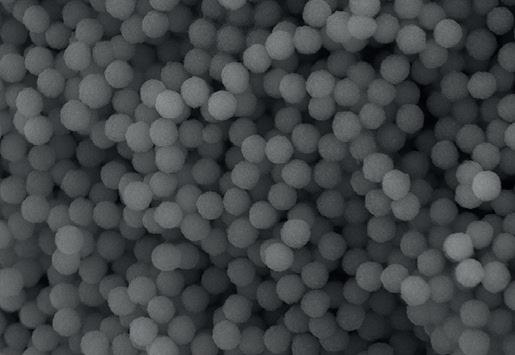

EthOss® is a 100% synthetic bone graft material for dental implant surgery. With no risk of cross-contamination, EthOss® works with the body’s healing process by creating a calciumrich environment and is completely absorbed.